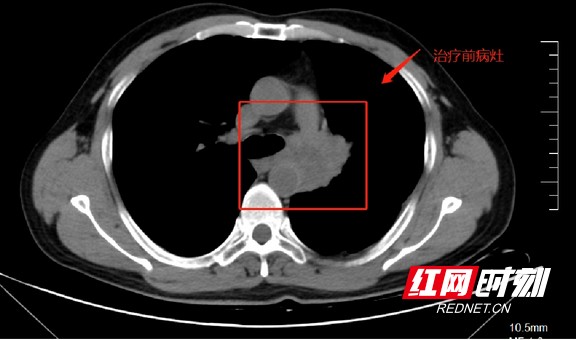

肿瘤科黄海主任在对姚叔进行了详细的询问会诊,让姚叔做了一次CT检查,因为姚叔没有把之前的CT片子带过来,不能直观地看到肿瘤的情况。CT检测结果出来后,显示姚叔的作左肺门处有54×39mm的软组织密度肿块影,左肺上叶支气管狭窄,左肺门及纵膈内见肿大淋巴结影,与上述肿块分界不清;左肺上下叶见斑片状模糊影;左下肺动脉狭窄。

患者检查影像。